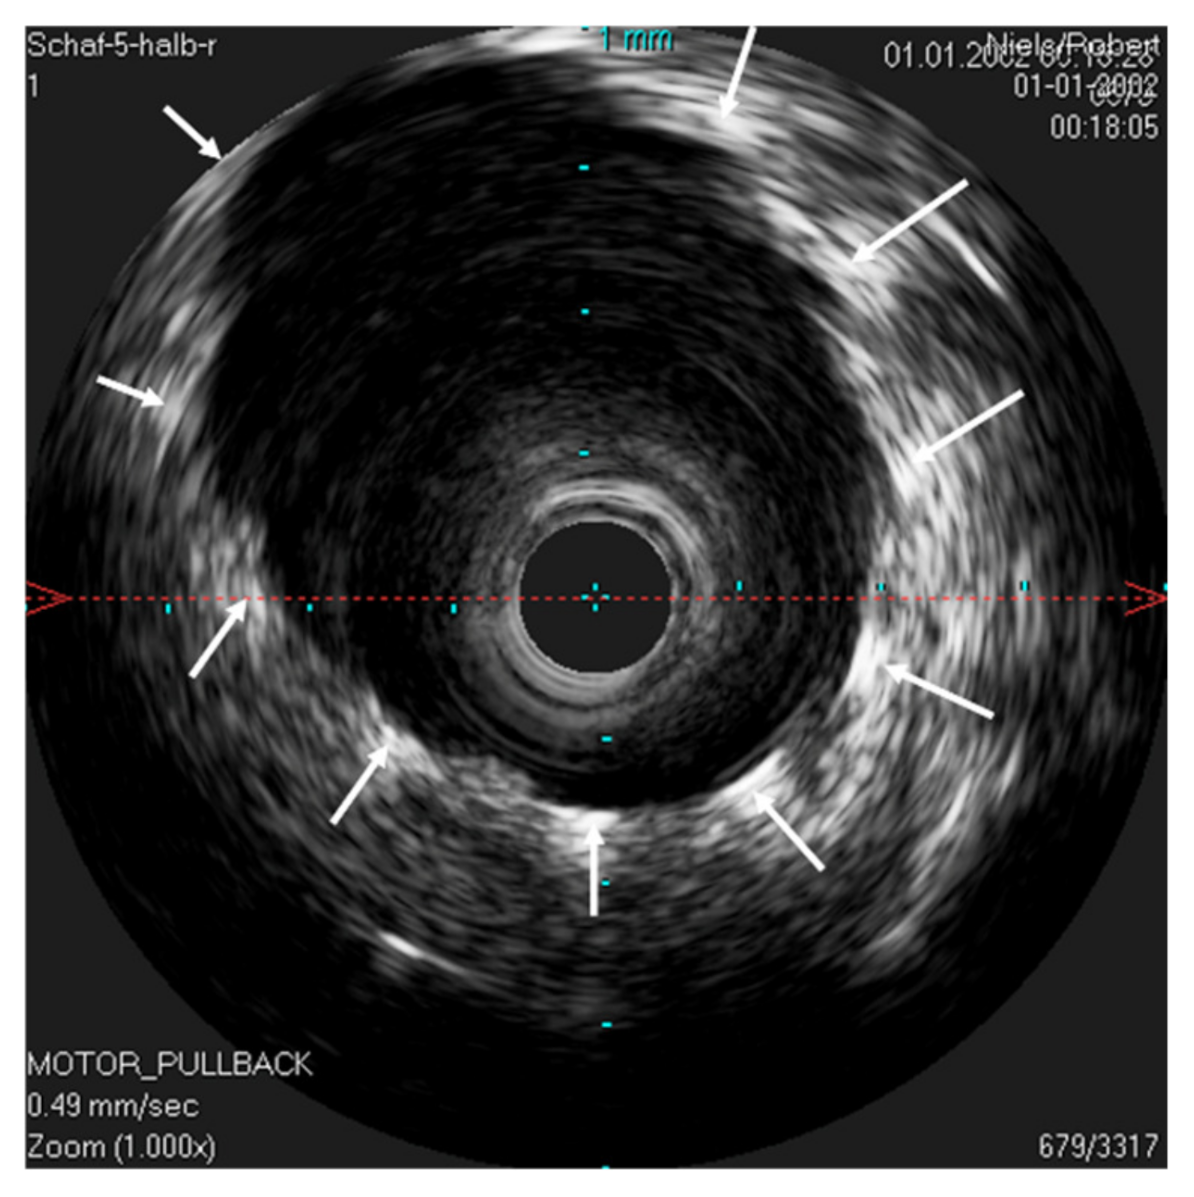

The IVUS provided a good image of the slit-formed shape of the ET (Figure 1) and the bony part with the isthmus (Figure 2) in the cross-section view. Bony structures and cartilage can be distinguished from the muscles and the Ostman fat pad. The signal transmission from the catheter to the tissue appeared to be good in all cases, even though the mucosal layer also caused some intense reflections. By flushing the ET with water (Figure 3), the lumen was more visible and became spindle shaped. Reflections at the mucosal layer were reduced.

Figure 7. Ultrasound image of the stented ET. The lumen of the ET is opened by the unfolded stent. The IVUS probe is located in the lumen of the stent. The stent struts can be seen echogenically, and sonic extinction is marked with white arrows. Note: the ET was flooded with water before the scan to allow for sonic coupling.